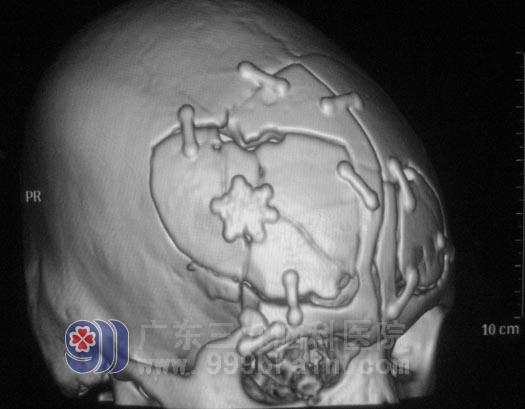

▲粉碎的颅骨

19岁的阿明,骑摩托车摔倒致头部外伤,头面部流血,意识障碍,被发现后急送当地医院救治,头颅CT检查提示“前额部硬脑膜下血肿,右侧额骨粉碎性骨折,右侧额叶脑内血肿”,给予清创、止血、脱水等对症治疗后,意识逐渐清醒,局部头皮肿胀,右侧眼睑肿胀、淤血,眼睑闭合不全,巩膜充血,结膜水肿。

在广东三九脑科医院综合神经外科复查CT提示:1.右侧额颞叶多发脑挫裂伤;2.额部硬膜外血肿形成;3.考虑胼胝体膝部轴索损伤;4.额骨右侧粉碎性骨折(部分颅骨碎片向颅内塌陷),并累及额窦窦壁、右侧眶上壁;右侧上颌骨多发骨折(累及右侧上颌窦窦壁、右侧上牙槽骨);双侧筛窦窦壁、右侧眼眶内侧壁多发骨折;5.右侧眼球突出,球后结构损伤;6.右侧上颌窦、筛窦、蝶窦、额窦内积血;7.右侧额颞部皮下软组织挫裂伤;8.寰枢椎关节半脱位可能。